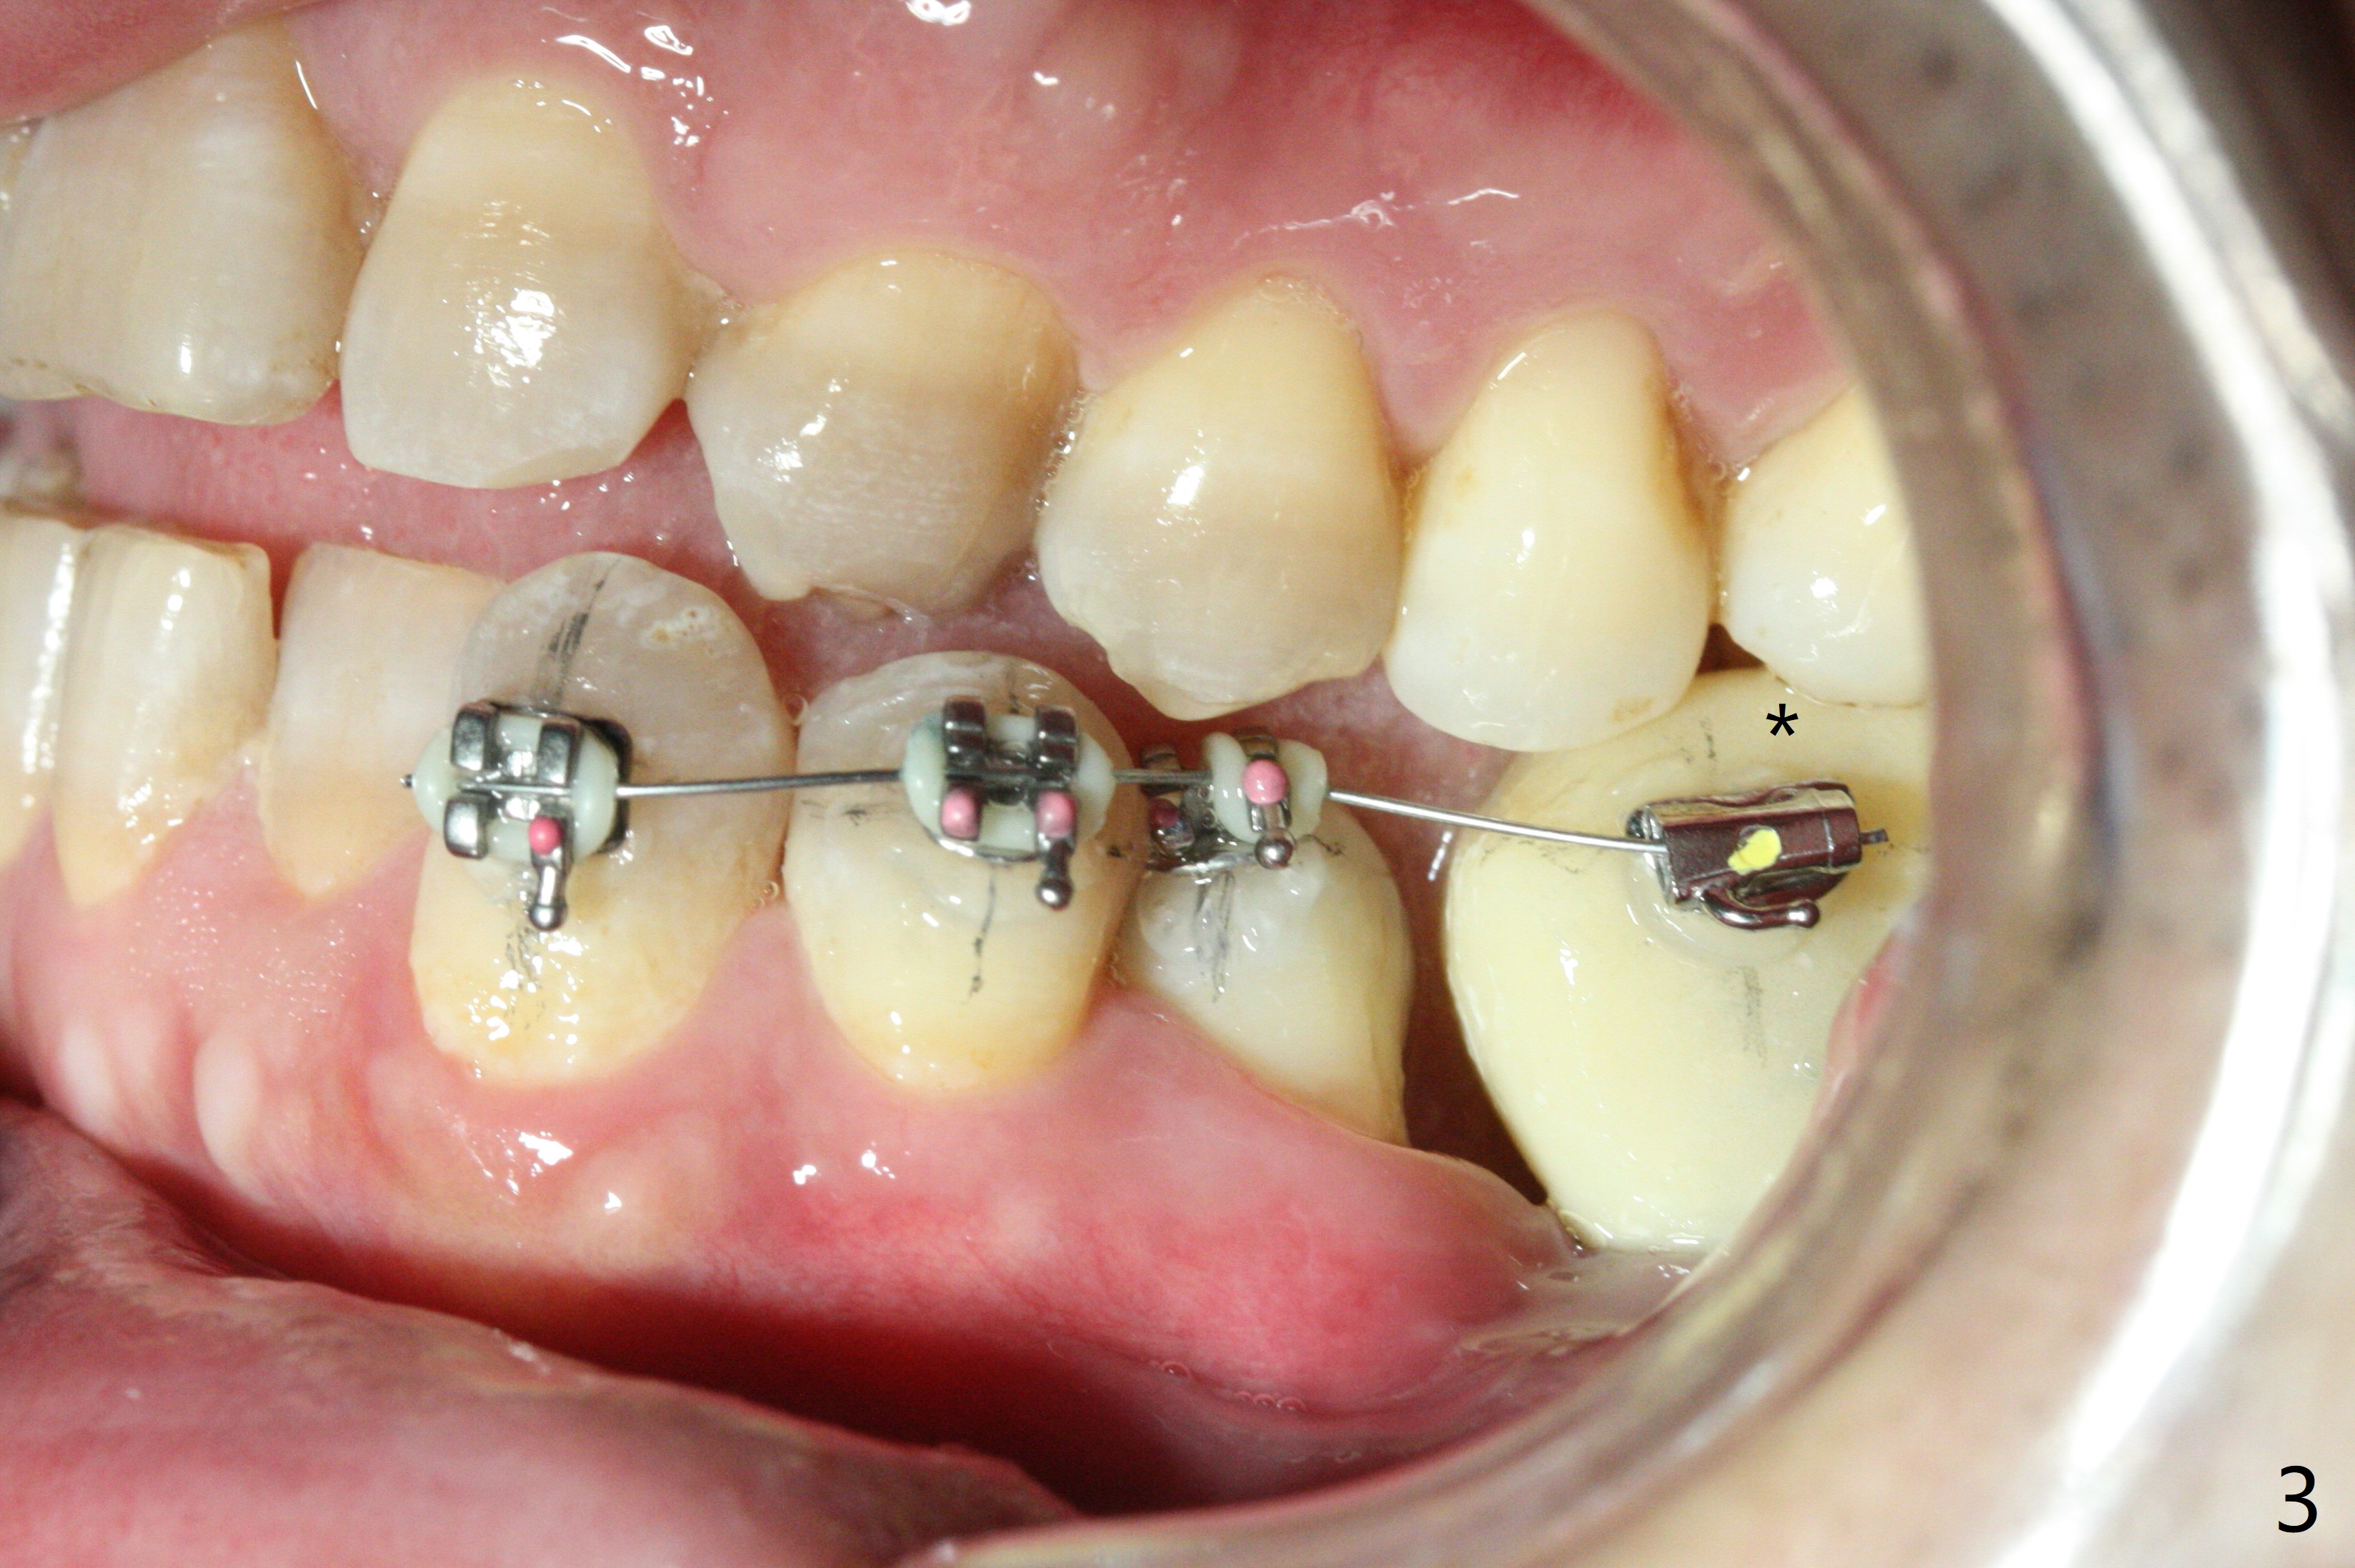

Two weeks post provisionalization over implants at #18 and 19 (4.5 months postop), acrylic is added to the provisional (Fig.1 *) and composite is placed on the other side (Fig.2 *) for clearance (Fig.3). Six days post bracketing, the diastema between LL5 and 6 decreases (Fig.4 between arrows, as compared to Fig.3), suggesting uprighting and distalization of the affected tooth. The diastema increases by trimming the mesial surface of LL6 provisional (Fig.5 *) prior to power chain placement. More acrylic is added to the occlusal surface of LL 6 and 7; more composite to that of UR3 (as compared to Fig.2) for clearance. Power chains change every week. LL5 is uprighted and distalized 1.5 months post banding (Fig.6,7 (14 niti)). Anterior brackets will be placed to correct LL2 cross bite next visit. Three weeks post open coil spring (5 months post initial banding), there is a space between LL2 and 3 (Fig.8) and between LL3/4 (Fig.9). The latter reduces instantly post power chain between LL3 and 6 (Fig.10). There is enough space for LL2 and sling shot is used to correct the cross bite 6.5 months post initial banding (Fig.11). The cross bite is corrected in 1.5 months after occlusal clearance is established (Fig.12). The lower left alignment is within normal limit, although in cross bite with the opposing dentition, immediate post molar crown cementation (Fig.13).